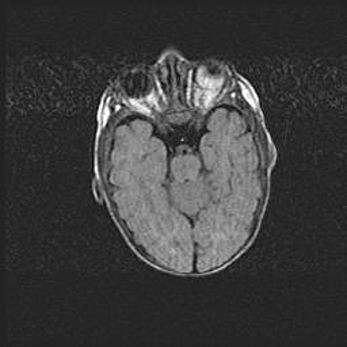

Множественные кисты обоих полушарий головного мозга, наибольшая из них в правой затылочной области. Ассиметричная атрофическая гидроцефалия.

Возраст: 7 месяцев

Вес: 5660 г

Пол: мужской

Окружность головы: 41,5 см

Срок гестации: 28-29 недель

Кисты головного мозга развиваются в результате многоочаговых некрозов вещества мозга и возникают вследствие перенесенной перинатальной инфекции, менингитов, энцефалитов, асфиксии, родовой травмы, расстройств мозгового кровообращения различного генеза. Образованию кист в веществе головного мозга плодов и новорожденных способствуют такие факторы, как высокое содержание в нем воды, недостаточная (или отсутствие) миелинизация и слабая астроглиальная реакция на повреждение.

Кисты могут сочетаться с гидроцефалией и другими поражениями головного мозга.